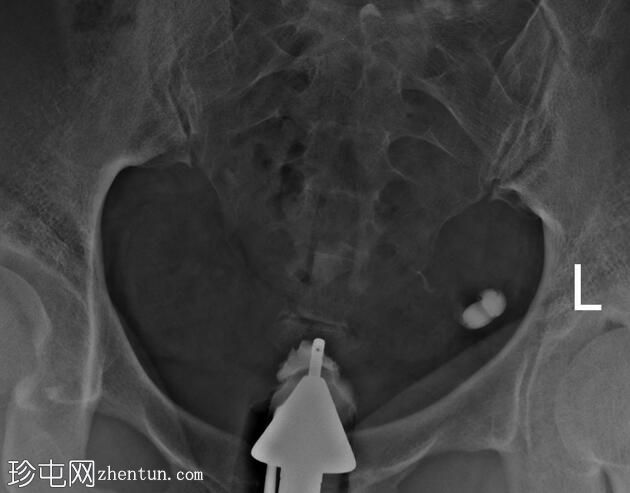

子宫体位于盆腔中线,形态及轮廓正常。

宫颈管长度正常,黏膜表面扩张良好。

右侧输卵管扩张并充满液体,无腹膜溢出,提示输卵管积水及输卵管阻塞。

左侧输卵管亦扩张并充满液体,伴有造影剂残留及少量溢出,提示输卵管积水及输卵管阻塞。

此外,左侧盆腔内,位于输卵管上内侧,可见大量分隔的造影剂积聚,并伴有盆腔输卵管周围粘连。

子宫输卵管造影结果符合双侧输卵管阻塞和输卵管积水,左侧输卵管周围可见分隔的造影剂渗漏。